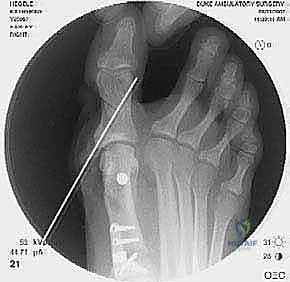

2. التصوير الشعاعي المتقدم

- الأشعة السينية مع تحمل الوزن (Weight-bearing X-rays): صور من الأمام، الجانب، والزوايا المائلة لتقييم زوايا العظام تحت تأثير وزن الجسم.

- تصوير السمسمانيات (Sesamoid view): لمعرفة ما إذا كانت العظام السمسمانية قد خُلعت من مكانها.

- الأشعة المقطعية (CT Scan): في الحالات المعقدة، يستخدم الدكتور هطيف الأشعة المقطعية ثلاثية الأبعاد لتقييم التئام العظام السابق، ومواقع المسامير القديمة، ودرجة خشونة المفاصل بدقة متناهية.

جراحة المراجعة هي عمل فني وهندسي معقد. إليك كيف يقوم الأستاذ الدكتور محمد هطيف بإجرائها خطوة بخطوة، معتمدًا على أحدث التقنيات العالمية:

- يتم تحديد مواقع المسامير أو الشرائح المعدنية من الجراحة السابقة وإزالتها (Hardware Removal). قد تكون هذه الخطوة صعبة إذا نما العظم فوق المسامير.

ج. إيثاق مفصل المشط السلامي الأول (First MTPJ Arthrodesis)

يُعتبر هذا الإجراء "المعيار الذهبي" (Gold Standard) وجراحة الإنقاذ النهائية في حالات المراجعة المعقدة، خاصة إذا كان المريض يعاني من:

* تدمير المفصل أو خشونة شديدة (التهاب المفاصل العظمي).

* فقدان عظمي كبير من الجراحة السابقة.

* تكرار شديد للتشوه مصحوب بألم مبرح.

في هذه العملية، يتم إزالة الغضروف التالف من مفصل الإصبع الكبير، ودمج العظام معًا في وضع مستقيم قليلاً للأعلى للسماح بالمشي الطبيعي. يتم التثبيت باستخدام شريحة ومسامير متقاطعة. النتيجة هي إصبع مستقيم، خالٍ تمامًا من الألم، ولا يمكن أن يعود للتشوه أبدًا.